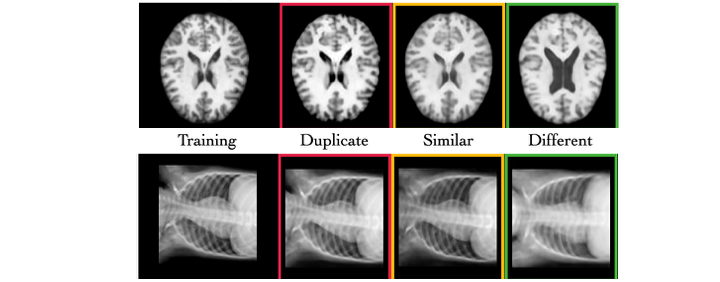

I grandi dataset di immagini mediche stanno diventando uno standard, ma resta una sfida cruciale: garantire...